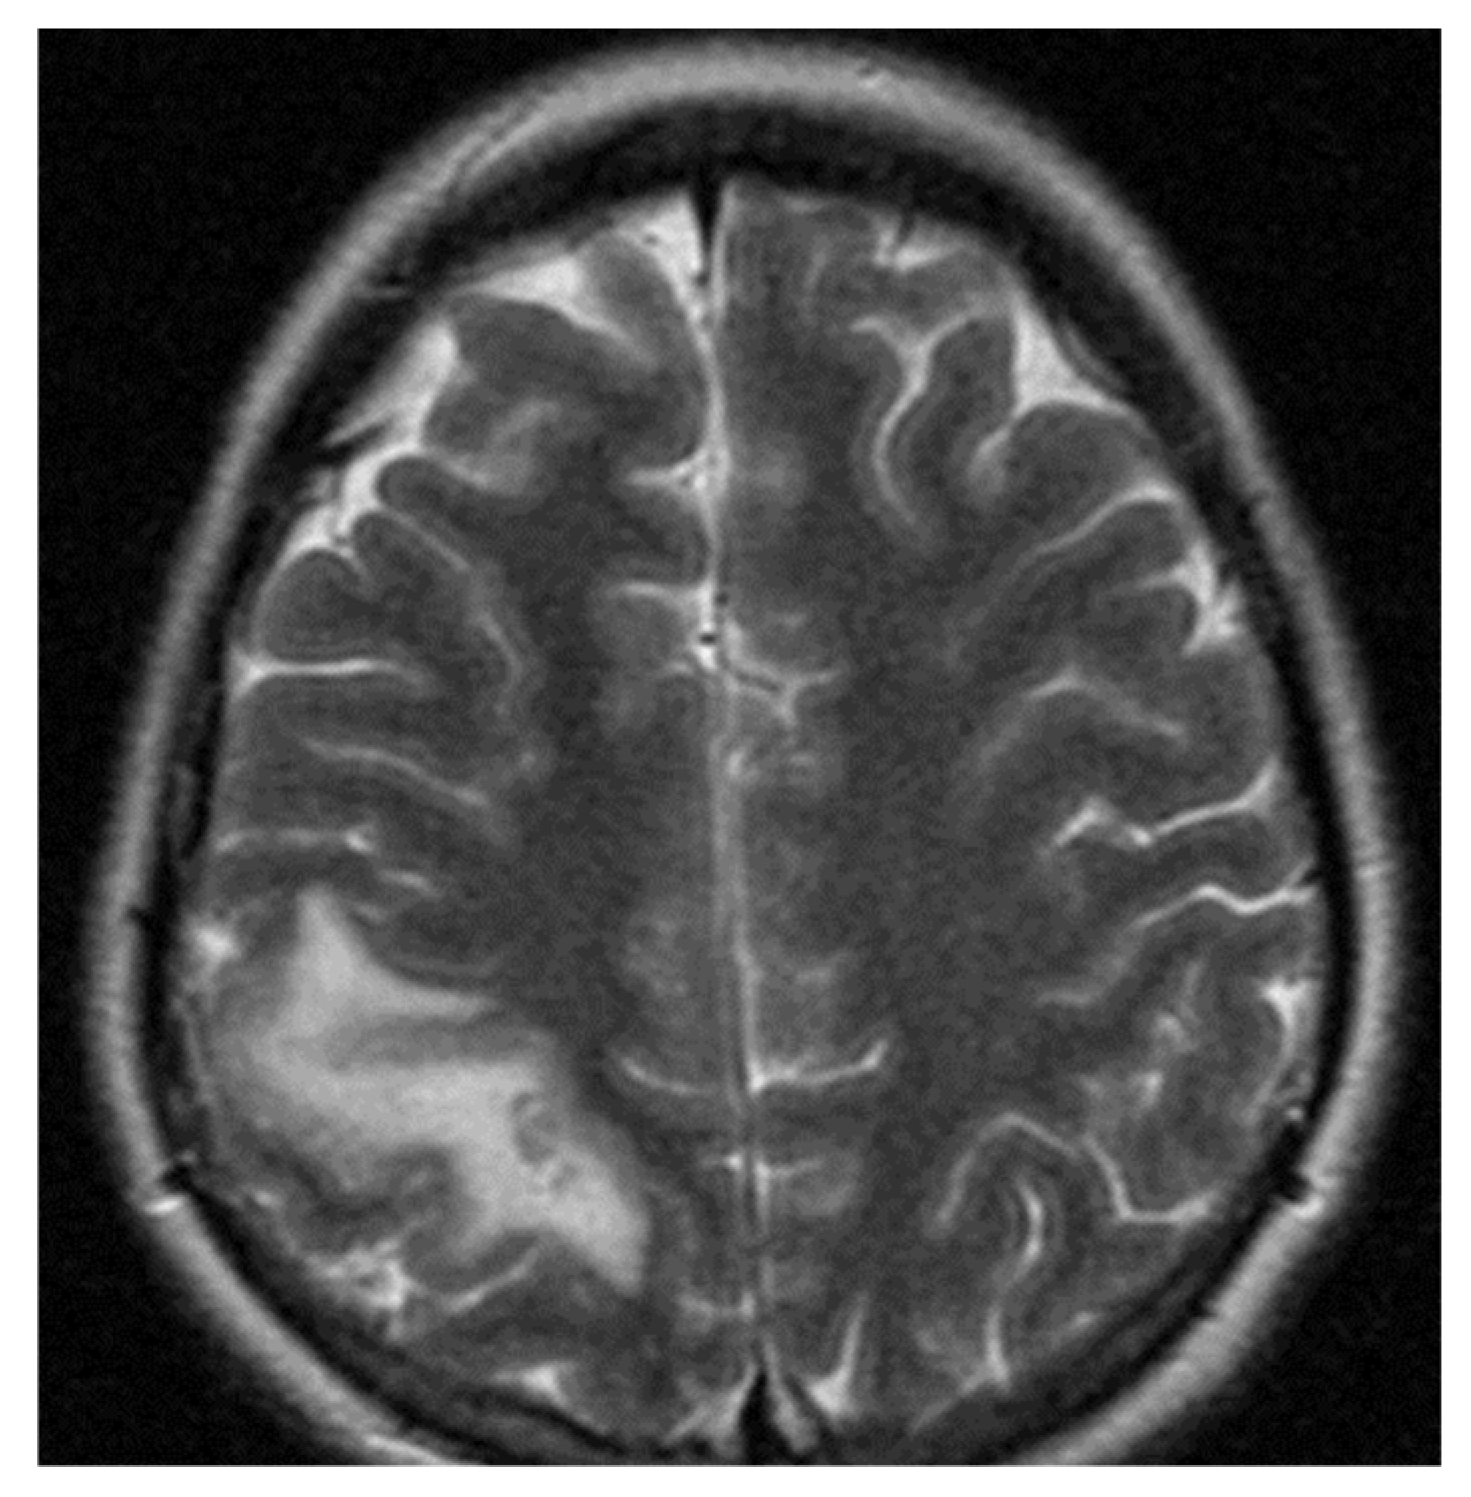

2.1.3. Neuroimaging